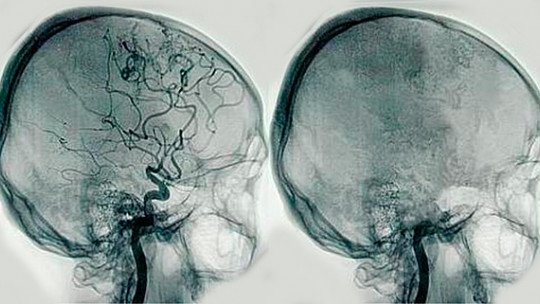

A angiografia (arteriografia) cerebral é uma técnica utilizada para a detecção de anomalias dos vasos sanguíneos cerebrais – como sejam uma dilatação arterial (aneurisma), uma inflamação (arterite), uma configuração anormal (malformação arteriovenosa) ou uma obstrução vascular (acidente vascular cerebral).

O exame é realizado por uma punção na artéria femoral (na perna) e através dela é introduzido um fino cateter, que chega até o local a ser estudado. Através do cateter é injetado contraste e pela radioscopia pode ser feito o diagnóstico necessário.